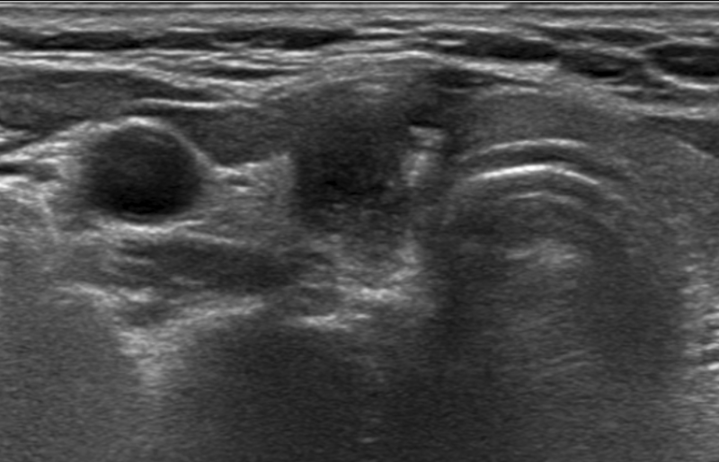

모든 시술 과정은 초음파 유도하에 시행됩니다. 또한, 국소마취만으로 시술이 가능하므로 외래 환자를 대상으로 시행될 수 있습니다. 갑상선 협부를 통해 굵은 주사 바늘을 결절 내부로 삽입하여 가능한 한 많은 내부 액체를 흡인한 후 적당량의 에탄올을 결절 내부로 주입합니다. 시술이 끝나면, 주사 바늘 천자 부위를 5-10분 정도 가볍게 압박합니다.

시술후